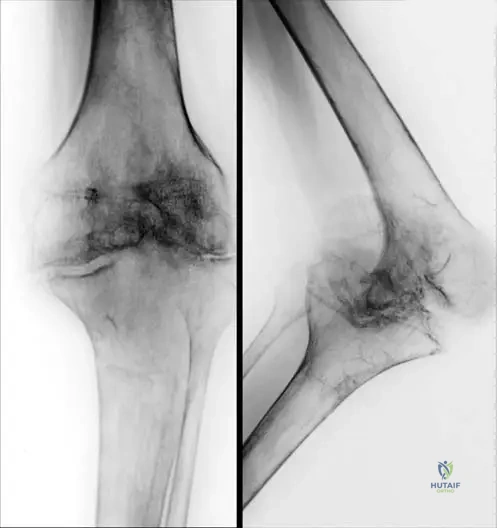

An 80-year-old man presents with increasing pain in his left tibia and a progressive bowing deformity of the leg. He also mentions that his hats no longer fit. Physical examination reveals a warm, thickened tibia. Laboratory tests show a significantly elevated alkaline phosphatase level. Radiographs of the tibia show cortical thickening, coarsened trabeculae, and areas of osteolysis and osteosclerosis, with a characteristic "blade of grass" or "V-shaped" lesion.

View Answer & Explanation

Correct Answer: D

Rationale: The clinical picture of bone pain, bowing deformity, increased hat size, elevated alkaline phosphatase, and characteristic radiographic findings of cortical thickening, coarsened trabeculae, and mixed lytic/sclerotic lesions is diagnostic of Paget’s Disease (Osteitis Deformans). Osteoporosis is characterized by decreased bone density. Osteomalacia involves defective mineralization. Hyperparathyroidism causes bone resorption. Osteopetrosis results in diffusely dense, brittle bones.